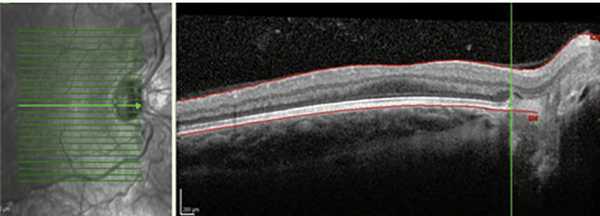

Рис. 2. Смещение ретинальных сосудов и эктопия макулы в носовую сторону (данные ОКТ).

Результаты проведенной ОКТ показали, что у глубоко недоношенных детей с благоприятными исходами РН на 33 (61%) из 54 глаз отмечалось нарушение анатомического контура макулы. На 12 глазах с остаточными изменениями I—II степени сглаженность фовеолярного контура в совокупности с сохранностью эмбрионального строения макулы (слоев нейроэпителия в фовеа) свидетельствовала о нарушении дифференцировки макулы вследствие недоношенности, и лишь на трех глазах она сопровождалась снижением остроты зрения ниже 0,3. На 10 глазах со II степенью РН сглаженность фовеолярного контура сопровождалась наличием структурных изменений (кистовидный отек и тракционная деформация нейроэпителия), невидимых при офтальмоскопии, что и объясняло некорригируемое снижение остроты зрения. При III степени РН сформированный фовеолярный контур и сохранность слоев нейроэпителия в макуле выявлены только на двух глазах. В остальных случаях фовеолярный контур был сглажен или отсутствовал вследствие тракционной деформации макулы после перенесенной РН и коррелировал со сниженной остротой зрения (рис. 7).

Рис. 7. Сглаженный фовеолярный контур и тракционная деформация сетчатки на глазу с рубцовой РН III степени.